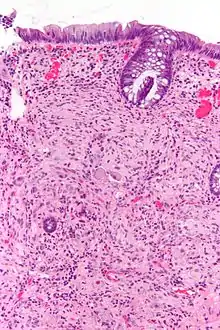

Pathology

Pathologically, ganglioneuromas are composed of ganglion cells, Schwann cells and fibrous tissue.[5] Ganglioneuromas are solid, firm tumours that typically are white when seen with the naked eye.